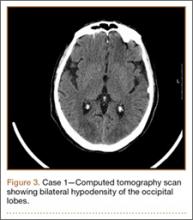

Development and Diagnosis of PRES. The patient made significant progress with physical therapy and developed episodes of hypertension at night on postoperative days 4 to 6. Her mean peak systolic blood pressure was 180 mm Hg. This improved after oral beta-blocker therapy. On postoperative day 6, the patient was ambulating with physical therapy and the aid of a walker. She was found to be neurologically intact, was resting comfortable in a chair reading a book, and was cleared for transfer to a rehabilitation facility the next day. During the morning on postoperative day 7, she developed confusion and visual loss. The patient reported blurry vision followed by complete bilateral painless loss of vision aside from mild light perception. She was unable to identify any objects. She had extinction to double simultaneous stimuli and evidence of agraphesthesia in the left hand. Her neurologic examination was otherwise at baseline. Upon emergent imaging, head CT showed bilateral symmetric areas of hypodensity involving the cortical and subcortical white matter of both occipital lobes (Figure 3). MRI showed extensive bilateral cortical and subcortical signal hyperintensity involving the parietal and occipital lobes (Figure 4). No evidence of petechial or lobar hemorrhage was found.